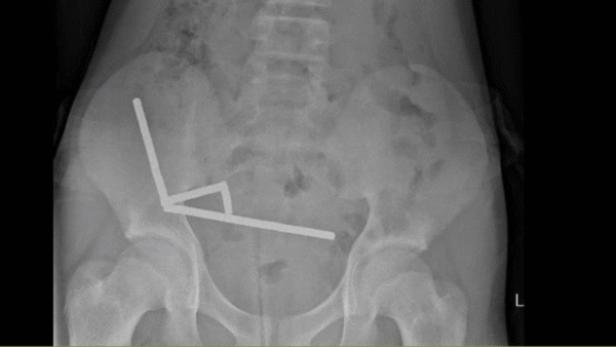

Die Magnete haben sich im Darmtrakt verbunden.

Der Teenager wurde mit Bauchschmerzen ins Spital eingeliefert und gestand dort, eine Woche zuvor etwa 80 bis 100 Magnete verschluckt zu haben. Durch ein Röntgen fanden die Ärzte heraus, dass sich die Magnete in seinem Verdauungstrakt zu 4 stabförmigen Gebilden verbunden zu haben.

Die Magnete mussten operativ entfernt werden, da sie Teile des Dünndarms und Blinddarms zusammendrückten und zu Gewebeschäden wegen Blutmangels, sogenannten Drucknekrosen, führten. Während der Operation sahen die Ärzte jedoch, dass es sich um fast 200 Magnete handelte. Wieso das Kind so viele Magnete verschluckt hatte, ist nicht bekannt.